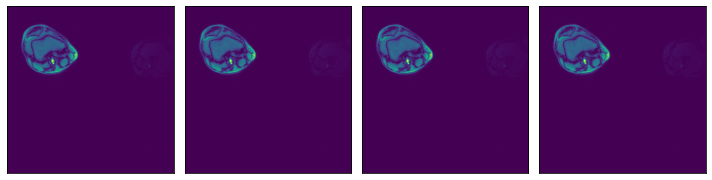

Specifying a subset of the array’s axes#

[11]:

@pipeline_def(batch_size=batch_size, num_threads=3, device_id=0)

def pipe_roi3(rel_roi_start, rel_roi_end, roi_axes):

data = fn.readers.numpy(

device="cpu",

file_root=data_dir,

files=files,

rel_roi_start=rel_roi_start,

rel_roi_end=rel_roi_end,

roi_axes=roi_axes,

)

return data

p1 = pipe_roi3(rel_roi_start=[0.1], rel_roi_end=[0.4], roi_axes=(0,))

data_roi3_1 = run(p1)

plot_batch(data_roi3_1)

p2 = pipe_roi3(rel_roi_start=[0.1], rel_roi_end=[0.4], roi_axes=(1,))

data_roi3_2 = run(p2)

plot_batch(data_roi3_2)

../../../../_images/examples_general_data_loading_numpy_reader_pipeline_mode_23_0.png

../../../../_images/examples_general_data_loading_numpy_reader_pipeline_mode_23_1.png